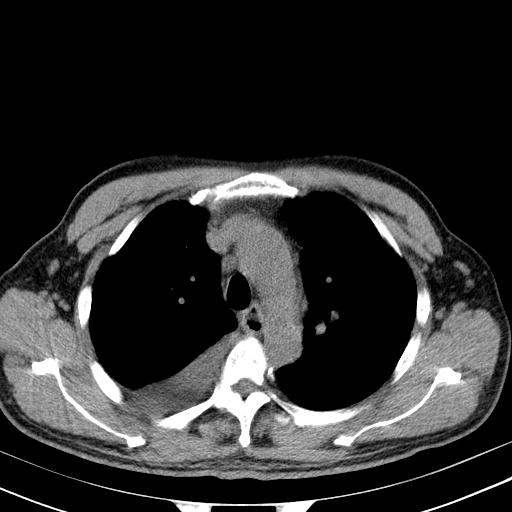

以下是引用zjzjr在2010-3-21 17:39:00的发言:[br]右下中心型肺癌并阻塞性肺炎/不张,纵膈淋巴结肿大,右侧大量胸腔积液,左侧少量胸腔积液

以下是引用zxl51642在2010-3-21 17:06:00的发言:[br]右下中心型肺癌并阻塞性肺炎/不张,纵膈淋巴结肿大,右侧大量胸腔积液,左侧少量胸腔积液,少量腹水。建议纤维支气管镜进一步检查。